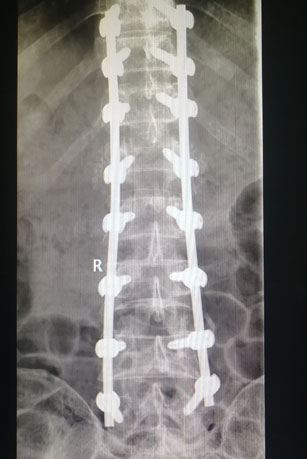

(天玑骨科机器人准确置入椎弓根螺钉)

侯克东带领手术团队首先完成手术路径的规划,并操作机器人进行手术三维定位,实施置钉。三维扫描影像显示螺钉位置精准无误,完全符合手术规划,最后圆满完成手术。此次手术的成功,意味着骨科机器人手术可以使很多高难度、高风险及复杂脊柱外科手术变得更加安全、高效、微创及智能。